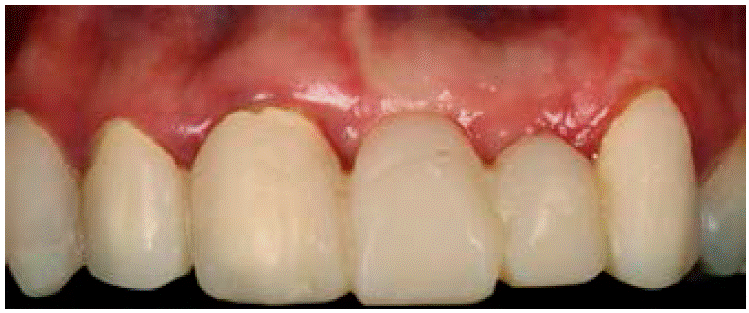

La paciente portaba una prótesis parcial removible en mal estado, que involucraba los órganos dentales 21 y 22 como se observa en la Figura 1. Además presentaba un defecto óseo de la cresta de tipo horizontal, clase 1 según la clasificación de Seibert: pérdida de tejido en dirección del vestibulopalatino (grosor) con altura adecuada como se muestra en las Figuras 2AyB.

Se decidió retirar la prótesis parcial removible previa a la cirugía y se le colocó un provisional de los órganos dentales 13 al 23 para disminuir tiempos quirúrgicos, favorecer una adecuada higiene y mejorar el aspecto dental de la paciente (Figura 5).